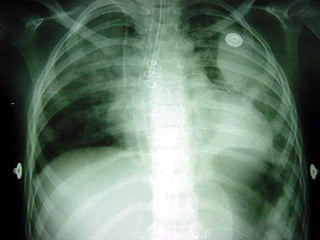

AnatomiaAnatomia